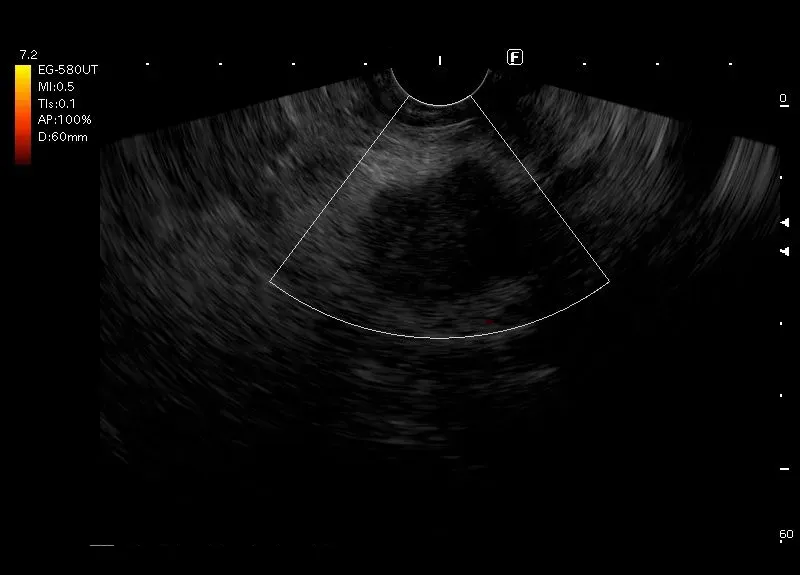

Zmiana położona w głowie trzustki, o niejednorodnie obniżonej echogeniczności, nierównych zarysach z widocznym o opcji  power doppler dyskretnym przepływem obwodowy a w elastografii  kodowaniem  na niebiesko - obraz guza trzustki.